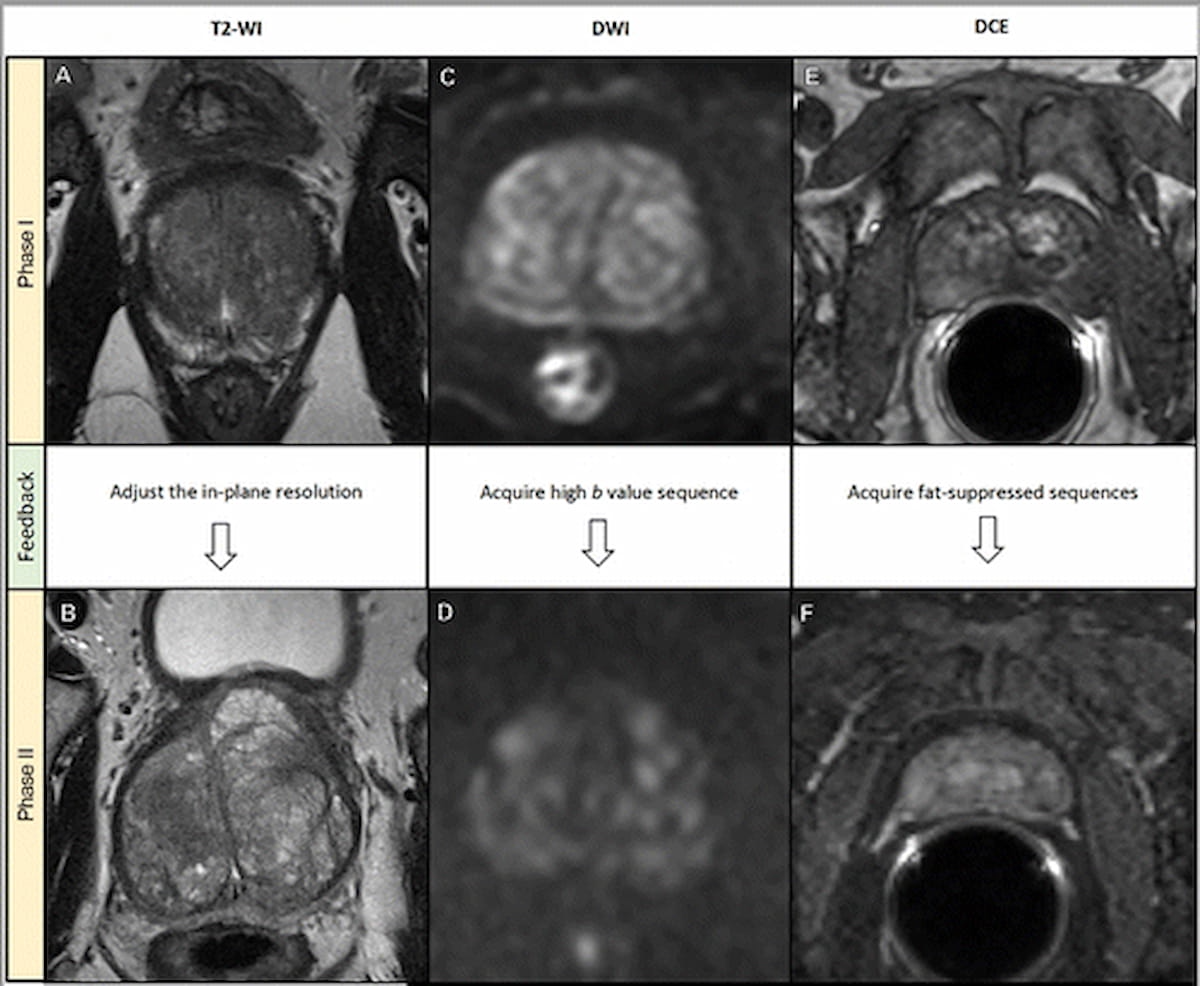

Here one can see before and after feedback on prostate MRI imaging quality with in-plane resolution changes for T2-weoghted imaging (A and B); a higher b value on diffusion-weighted imaging (C and D); and the addition of fat suppression on dynamic contrast-enhanced MRI (E and F). (Images courtesy of Radiology.)

In the second phase of the study, researchers provided feedback to centers that did not achieve optimal PI-QUAL scoring. The most common recommendations for improvement for prostate MRI imaging were as follows:

• adjusting temporal resolution to a maximum of 15 seconds for DCE imaging (56 percent);

• inclusion of an acquired/calculated high b value of greater than 1400 sec/mm2 for DWI sequences (40 percent)

• utilizing fat suppression sequences for DCE imaging (33 percent); and

• adjusting in-plane resolution as per PI-RADS 2.1 guidelines for T2-weighted imaging (21 percent).